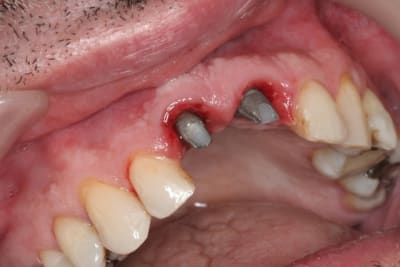

juste pour illustrer mon propos....

ici une MCI ou plutôt, devrais je dire une vis de cica anatomique immédiate.